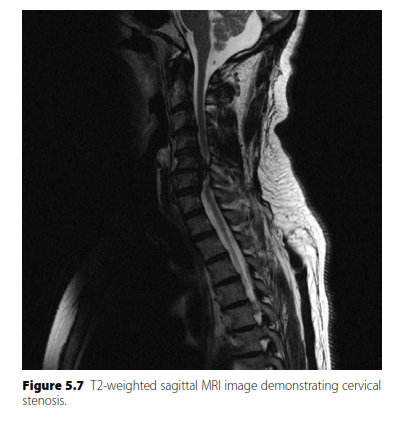

MRI of the lumbar spine is the gold standard imaging study for diagnosing lumbar spinal stenosis. It provides excellent visualization of soft tissues, including the neural elements, ligamentum flavum, disc bulges, and allows for accurate assessment of the spinal canal and neural foramina narrowing. Plain radiographs (Option A) can show degenerative changes but not soft tissue compression. CT (Option B) is good for bone but inferior to MRI for neural structures unless MRI is contraindicated. EMG/NCS (Option D) and epidural injections (Option E) are diagnostic/therapeutic adjuncts, not primary imaging modalities for initial diagnosis.